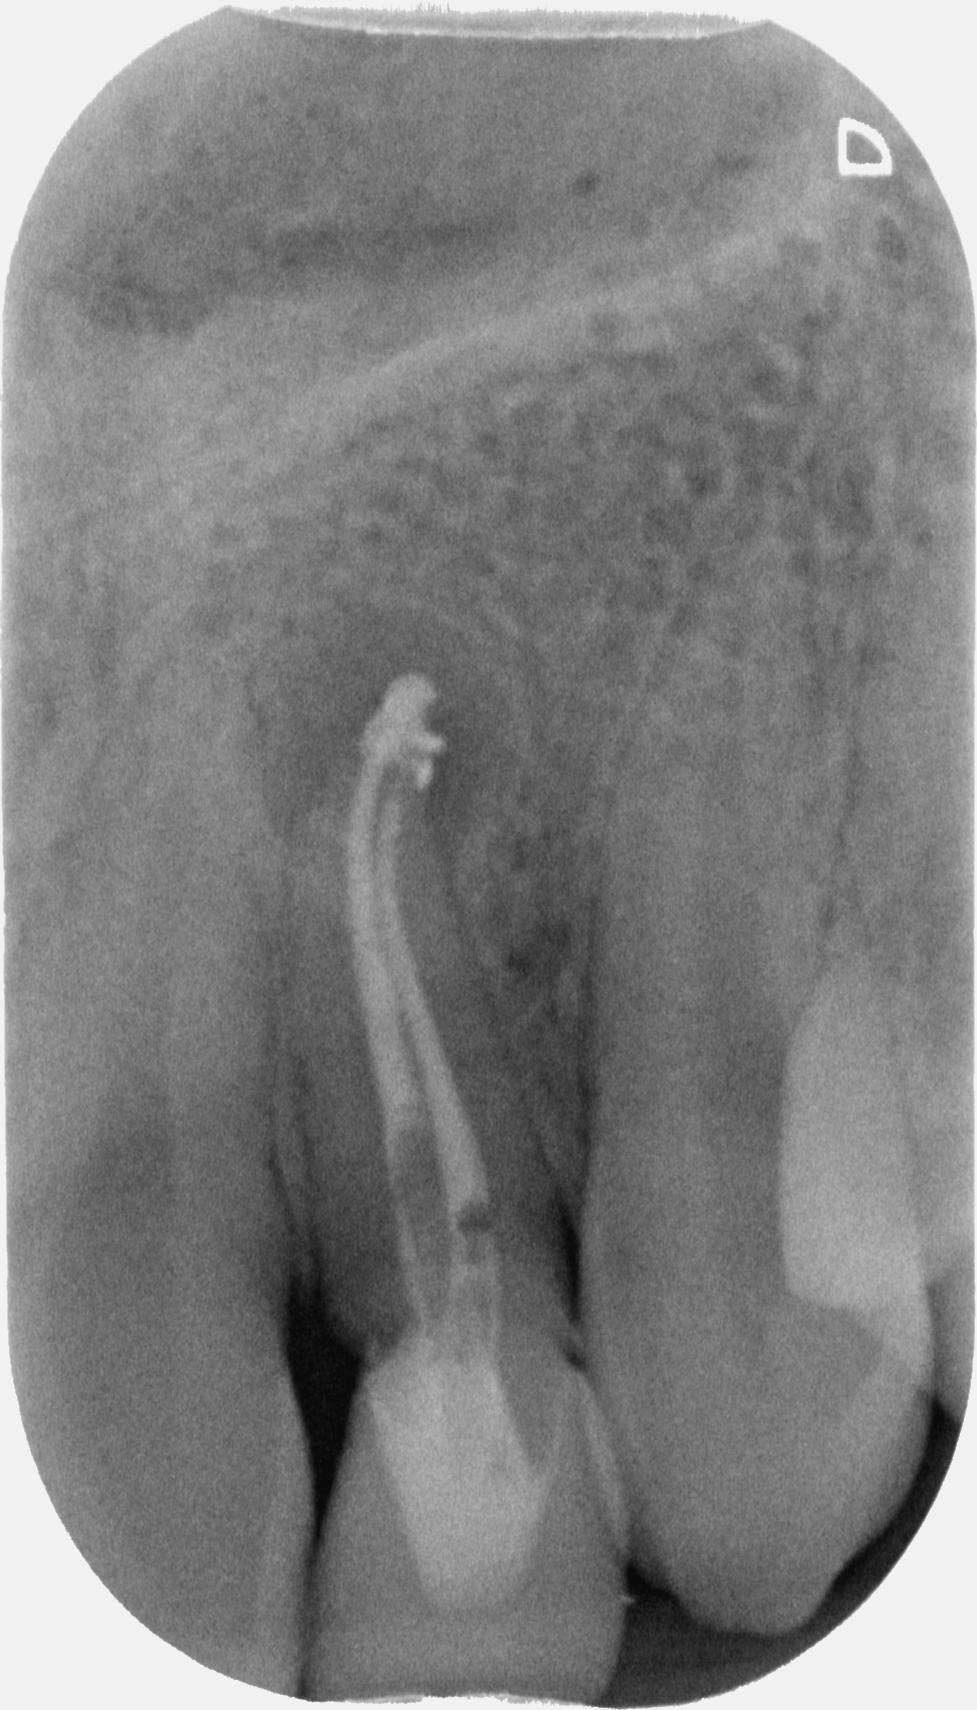

Con l’ausilio della Cone Beam sono riuscito a identificare che il dente aveva due canali e una radice molto palatoversa: per accedere a questi canali, separati tra loro dall’istmo di smalto invaginato, potevo fare una cavità perpendicolare al dente a livello vestibolare e una palatina.

Una volta trovato il canale con l’accesso più difficile e sapendo che un secondo canale decorreva parallelo a questo dal lato palatino il resto è stato relativamente semplice.

Un mio collaboratore che mi assisteva mentre eseguivo il trattamento, dapprima ammirato e affascinato come me dal caso, alla fine dello stesso ha convenuto con me che in termini pratici non era affatto difficile, a conti fatti.

La cosa più complicata in endodonzia, come ti spiegavo in un precedente articolo, è previsualizzare il trattamento e avere una strategia ben chiara in testa prima di cominciare un trattamento, ricordi?